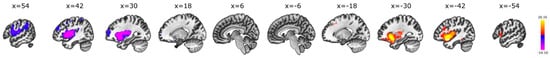

3.1. Seed-to-Voxel